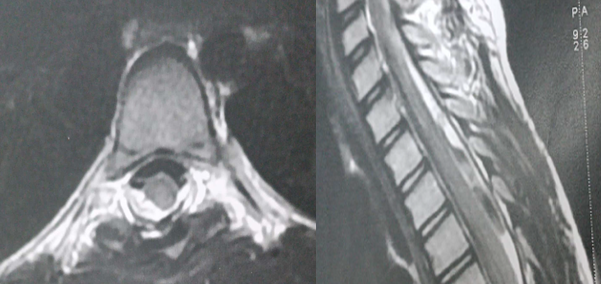

The MRI revealed an intradural extramedullary posterior cystic lesion at level of the thoracic spine, harmonious well-demarcated, that demonstrated low signal intensity on T1 and high signal intensity on T2 weighted images mimicking Cerebrospinal Fluid (CSF). The lesion appeared to be an AC (Figure 1) pushing forward the cord. There was no enhancement neither bony change.

Figure 1. MRI of the thoracic spine shows a cystic lesion mimicking CSF signal (black star) compressing the spinal cord